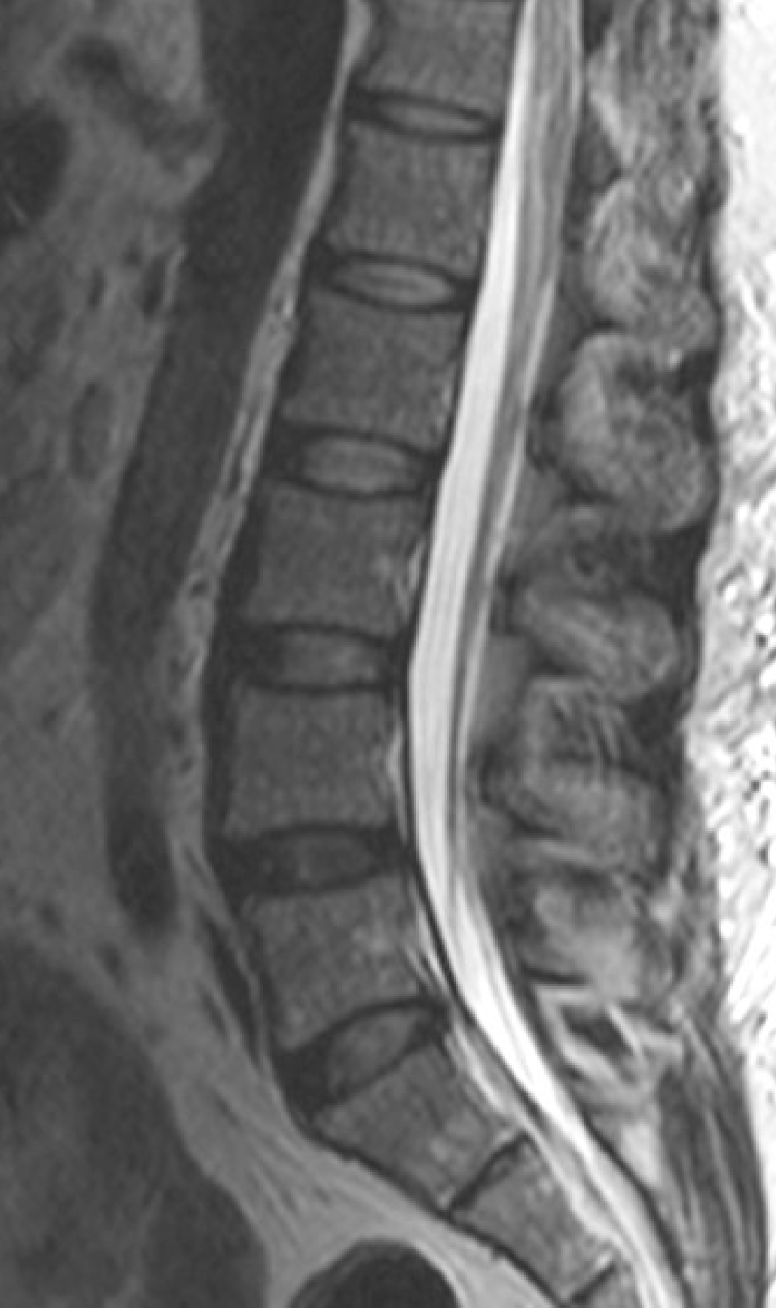

• location: enclosed by vertebrae in the vertebral canal

foramen magnum to L1-2

spinal cord begins at _______ ______ where it meets the medulla, and ends at intervertebral disc between regions ____

conus medullaris

• tapered, cone-shaped

• distal portion of spinal cord

<ul><li><p>tapered, cone-shaped</p></li><li><p>distal portion of spinal cord</p></li></ul><p></p>

cauda equina

• strands of fibers: “horse’s tail”

• extends from the distal end of the spinal cord

• composed of nerve roots

<ul><li><p>strands of fibers: “horse’s tail”</p></li><li><p>extends from the distal end of the spinal cord</p></li><li><p>composed of nerve roots</p></li></ul><p></p>

filum terminale

• extension of pia mater

• long, thin strip of CT

• extens inferiorly from conus medullaris

• anchors cord to coccyx

<ul><li><p>extension of pia mater</p><ul><li><p>long, thin strip of CT</p></li></ul></li><li><p>extens inferiorly from conus medullaris</p></li><li><p>anchors cord to coccyx</p></li></ul><p></p>

cervical and lumbar enlargements

• thickened regions of the spinal cord

• additional neurons to supply limbs

<ul><li><p>thickened regions of the spinal cord</p></li><li><p>additional neurons to supply limbs</p></li></ul><p></p>